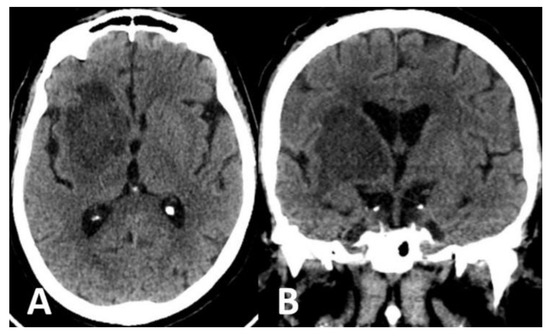

Computed tomography (CT) scan of the brain revealed the presence of a focal space-occupying hypodense lesion in the right basal ganglia, surrounded by edema. The lesion caused mass effect with effacement of ipsilateral cerebral sulci, buckling of the ventricular system (without hydrocephalus) and mild deviation of midline structures to the left (Figure 1). On magnetic resonance imaging (MRI), the lesion was relatively heterogeneous on T2/FLAIR and exhibited marginal enhancement following gadolinium injection. Perfusion-weighted imaging demonstrated significant decrease of cerebral blood flow (CBV) within the lesion (Figure 2). Following imaging characterization of the lesion, an intraoperative consultation with brain biopsy was performed through a right parietal burr hole. A brain smear revealed the presence of brain tissue with abundant dirty necrosis and predominantly acute inflammatory cells. Cystic structures containing encapsulated microorganisms were also identified, raising the hypothesis of TG infection. A brain biopsy was later performed and revealed not only cysts containing bradyzoites but also free microorganisms (tachyzoites) across the sample. Immunohistochemical staining with antibodies against TG confirmed the diagnosis of cerebral toxoplasmosis, highlighting the free tachyzoites (Figure 3). A post-biopsy CT scan excluded procedure-related complications.

Figure 2.

MRI of the brain showed a heterogeneous lesion on the T2/FLAIR sequence (A), displaying ring-enhancement after gadolinium injection (B). Perfusion-weighted imaging showed significant decrease of CBV (C) within the lesion.

The differential diagnosis of cerebral toxoplasmosis is extensive and includes lymphoma, metastasis and other opportunistic infections, as these entities may share similar imaging features [2]. Nonetheless, the presence of a small mural nodule within the ring-enhancing lesion (“eccentric target sign”) and/or the existence of concentric alternating zones of hypo and hyperintensity on MRI (“concentric target sign”) suggest the diagnosis of toxoplasmosis [16]. Moreover, low metabolic activity on thallium single-photon emission computed tomography (SPECT) and/or positron emission tomography (PET) and decreased CBV on perfusion-weighted MRI favor the hypothesis of a pseudotumoral mass (such as infection) instead of a brain tumor or metastasis [2].